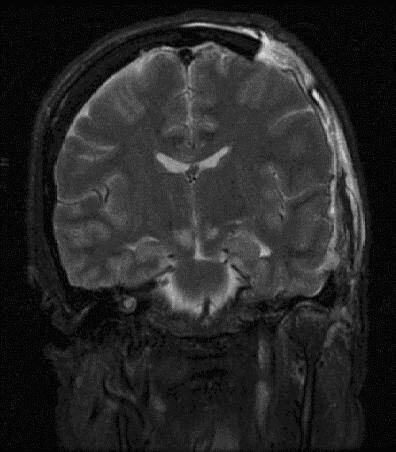

Π’ΠΊΠ»ΠΈΠ½Π΅Π½ΠΈΠ΅ Π³ΠΎΠ»ΠΎΠ²Π½ΠΎΠ³ΠΎ ΠΌΠΎΠ·Π³Π° β€” это ΠΆΠΈΠ·Π½Π΅ΡƒΠ³Ρ€ΠΎΠΆΠ°ΡŽΡ‰Π΅Π΅ состояниС, Π²ΠΎΠ·Π½ΠΈΠΊΠ°ΡŽΡ‰Π΅Π΅ ΠΏΡ€ΠΈ смСщСнии структур ΠΌΠΎΠ·Π³Π° Ρ‡Π΅Ρ€Π΅Π· СстСствСнныС отвСрстия Ρ‡Π΅Ρ€Π΅ΠΏΠ° вслСдствиС Ρ€Π΅Π·ΠΊΠΎΠ³ΠΎ ΠΏΠΎΠ²Ρ‹ΡˆΠ΅Π½ΠΈΡ Π²Π½ΡƒΡ‚Ρ€ΠΈΡ‡Π΅Ρ€Π΅ΠΏΠ½ΠΎΠ³ΠΎ давлСния (Π’Π§Π”). Оно развиваСтся ΠΏΡ€ΠΈ Ρ‡Π΅Ρ€Π΅ΠΏΠ½ΠΎ-ΠΌΠΎΠ·Π³ΠΎΠ²Ρ‹Ρ… Ρ‚Ρ€Π°Π²ΠΌΠ°Ρ…, опухолях, кровоизлияниях ΠΈΠ»ΠΈ ΠΎΡ‚Π΅ΠΊΠ΅ ΠΌΠΎΠ·Π³Π° ΠΈ Ρ‚Ρ€Π΅Π±ΡƒΠ΅Ρ‚ Π½Π΅ΠΌΠ΅Π΄Π»Π΅Π½Π½ΠΎΠ³ΠΎ Π²ΠΌΠ΅ΡˆΠ°Ρ‚Π΅Π»ΡŒΡΡ‚Π²Π° для прСдотвращСния Π½Π΅ΠΎΠ±Ρ€Π°Ρ‚ΠΈΠΌΡ‹Ρ… ΠΏΠΎΠ²Ρ€Π΅ΠΆΠ΄Π΅Π½ΠΈΠΉ ствола ΠΌΠΎΠ·Π³Π° ΠΈ смСрти. ΠšΠ»ΡŽΡ‡Π΅Π²Ρ‹ΠΌΠΈ ΠΏΡ€ΠΈΠ·Π½Π°ΠΊΠ°ΠΌΠΈ вклинСния ΡΠ²Π»ΡΡŽΡ‚ΡΡ ΠΏΡ€ΠΎΠ³Ρ€Π΅ΡΡΠΈΡ€ΡƒΡŽΡ‰Π΅Π΅ ΡƒΠ³Π½Π΅Ρ‚Π΅Π½ΠΈΠ΅ сознания: ΠΎΡ‚ спутанности Π΄ΠΎ ΠΊΠΎΠΌΡ‹, ΡΠΎΠΏΡ€ΠΎΠ²ΠΎΠΆΠ΄Π°ΡŽΡ‰Π΅Π΅ΡΡ Π°Π½ΠΈΠ·ΠΎΠΊΠΎΡ€ΠΈΠ΅ΠΉ (Π½Π΅Ρ€Π°Π²Π½ΠΎΠΌΠ΅Ρ€Π½Ρ‹ΠΌ Ρ€Π°ΡΡˆΠΈΡ€Π΅Π½ΠΈΠ΅ΠΌ Π·Ρ€Π°Ρ‡ΠΊΠΎΠ²), ΠΏΡ€ΠΈΡ‡Π΅ΠΌ Π·Ρ€Π°Ρ‡ΠΎΠΊ Π½Π° сторонС пораТСния пСрСстаСт Ρ€Π΅Π°Π³ΠΈΡ€ΠΎΠ²Π°Ρ‚ΡŒ Π½Π° свСт. Π₯Π°Ρ€Π°ΠΊΡ‚Π΅Ρ€Π½Ρ‹ патологичСскиС Ρ‚ΠΈΠΏΡ‹ дыхания (Π§Π΅ΠΉΠ½Π°-Бтокса, апнСйстичСскоС), брадикардия Π½Π° Ρ„ΠΎΠ½Π΅ Π³ΠΈΠΏΠ΅Ρ€Ρ‚Π΅Π½Π·ΠΈΠΈ (Β«Ρ‚Ρ€ΠΈΠ°Π΄Π° ΠšΡƒΡˆΠΈΠ½Π³Π°Β»), Π° Ρ‚Π°ΠΊΠΆΠ΅ Ρ€ΠΈΠ³ΠΈΠ΄Π½ΠΎΡΡ‚ΡŒ Π·Π°Ρ‚Ρ‹Π»ΠΎΡ‡Π½Ρ‹Ρ… ΠΌΡ‹ΡˆΡ† ΠΈ дСкортикационная/дСцСрСбрационная ΠΏΠΎΠ·Π° (нССстСствСнноС ΠΏΠΎΠ»ΠΎΠΆΠ΅Π½ΠΈΠ΅ конСчностСй). ΠŸΡ€ΠΈ Ρ‚Ρ€Π°Π½ΡΡ‚Π΅Π½Ρ‚ΠΎΡ€ΠΈΠ°Π»ΡŒΠ½ΠΎΠΌ Π²ΠΊΠ»ΠΈΠ½Π΅Π½ΠΈΠΈ часто Π½Π°Π±Π»ΡŽΠ΄Π°Π΅Ρ‚ΡΡ Π³Π΅ΠΌΠΈΠΏΠ°Ρ€Π΅Π· Π½Π° сторонС, ΠΏΡ€ΠΎΡ‚ΠΈΠ²ΠΎΠΏΠΎΠ»ΠΎΠΆΠ½ΠΎΠΉ ΠΏΠΎΡ€Π°ΠΆΠ΅Π½ΠΈΡŽ, Π° ΠΏΡ€ΠΈ Π²ΠΊΠ»ΠΈΠ½Π΅Π½ΠΈΠΈ ΠΌΠΈΠ½Π΄Π°Π»ΠΈΠ½ ΠΌΠΎΠ·ΠΆΠ΅Ρ‡ΠΊΠ° Π² большоС Π·Π°Ρ‚Ρ‹Π»ΠΎΡ‡Π½ΠΎΠ΅ отвСрстиС β€” остановка дыхания ΠΈΠ·-Π·Π° компрСссии ΠΏΡ€ΠΎΠ΄ΠΎΠ»Π³ΠΎΠ²Π°Ρ‚ΠΎΠ³ΠΎ ΠΌΠΎΠ·Π³Π°.